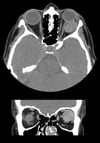

На этом изображении на КТ-сканах в аксиальной (вверху) и корональной (внизу) проекциях показана четко очерченная опухоль в интракональном пространстве за левым глазным яблоком. Это образование представляет собой кавернозную венозную мальформацию.